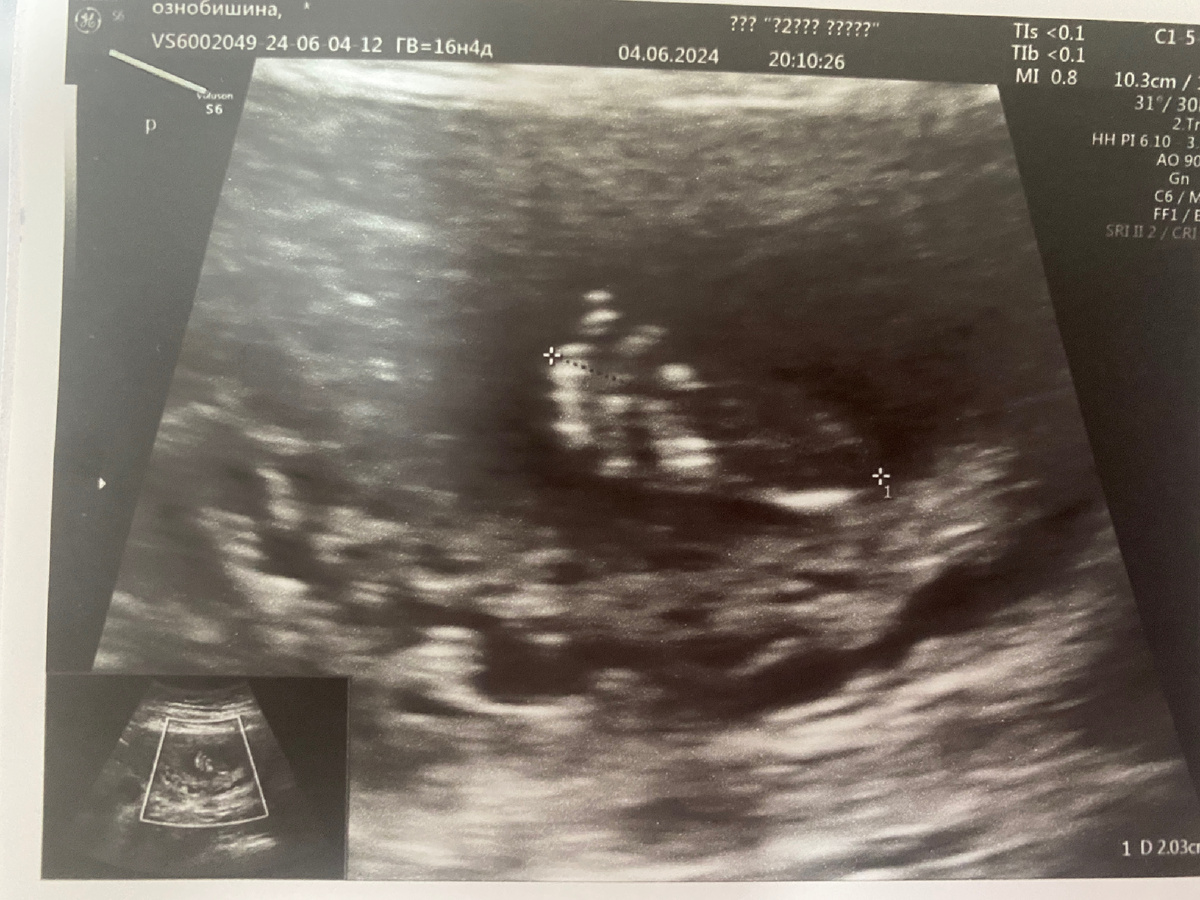

Как все начиналось.     На последних сроках, начиная с 32 недели, я как обычно пошла на узи (ходила платно, помимо ЖК) до этого все было прекрасно, но вот тут мне говорят: «Нарушение маточного кровотока слева, это вам к гинекологу, ничего страшного». Ну раз ничего страшного, я хожу дальше и ни о чем не думаю, все равно к врачу на служащей неделе, но тут, я и моя тревожность, решили почитать об этом кровотоке, после чего, я пулей на следующий день бегу к платному гинекологу. Она меня осмотрела и как и все сказала, что живот маленький, и рассказала об этом самом нарушении.     У меня через пару дней день рождение должно было быть, но было совершено не до него, гинеколог сказала ехать в мою ЖК и брать направление в роддом, что я и сделала в тот же вечер.    Взяла направление, собрала вещи и купила еды (я лежала в больнице последний раз 20 лет назад) взяла, чтобы уж наверняка😅 и на следующий день я поехала к 9 утра в роддом. Там в приемном меня осмотрели и положили в дородовое. Ждала п

Взяла направление, собрала вещи и купила еды (я лежала в больнице последний раз 20 лет назад) взяла, чтобы уж наверняка😅 и на следующий день я поехала к 9 утра в роддом. Там в приемном меня осмотрели и положили в дородовое. Ждала палату я минут 30, мне выдали постельное, и я заселилась, познакомилась с соседкой. Позвали на узи и говорят: «А у вас все хорошо с кровотоками, ребёнок в норме, но немного маловат, но мы вас все равно положим на 5 дней».

Ровно через месяц, я снова иду на платное узи и снова тоже самое, срок уже 36 недель. Естественно меня определяют снова в роддом, все тоже самое, только КТГ каждый день. Снова узи в роддоме и снова все хорошо, НО говорят, что ребёнок маловесный, на тот момент 2 кг всего, я все также лежу и меня выписывают через 5 дней.